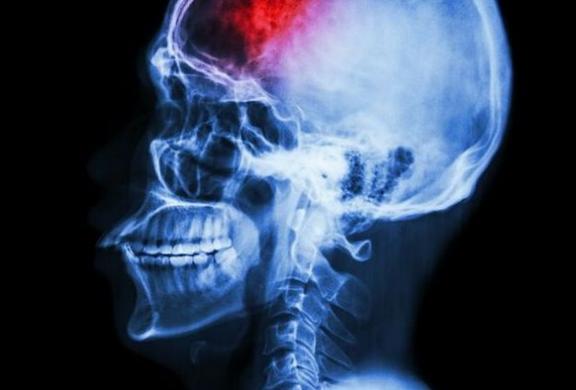

ΕΓΚΕΦΑΛΙΚΟ: ΟΙ ΤΡΕΙΣ ΒΑΣΙΚΕΣ ΕΝΔΕΙΞΕΙΣ ΠΟΥ ΠΡΕΠΕΙ ΝΑ ΣΑΣ ΚΙΝΗΤΟΠΟΙΗΣΟΥΝ

Τα εγκεφαλικά αποτελούν την τρίτη βασική αιτία θανάτου στη Δύση μετά την καρδιοπάθεια και τον καρκίνο, ενώ σε εκατομμύρια ανθρώπους αφήνουν κάποια μορφή αναπηρίας.

Περίπου 75% των εγκεφαλικών είναι ισχαιμικά και οφείλονται σε θρόμβους που αποφράσσουν κάποια αρτηρία, η οποία τροφοδοτεί με αίμα τον εγκέφαλο. Τα ισχαιμικά εγκεφαλικά επεισόδια λέγονται επίσης θρομβοεμβολικά.

Οι άλλες περιπτώσεις εγκεφαλικών επεισοδίων οφείλονται σε ρήξη κάποιας αρτηρίας που τροφοδοτεί με αίμα τον εγκέφαλο και αποκαλούνται αιμορραγικά.